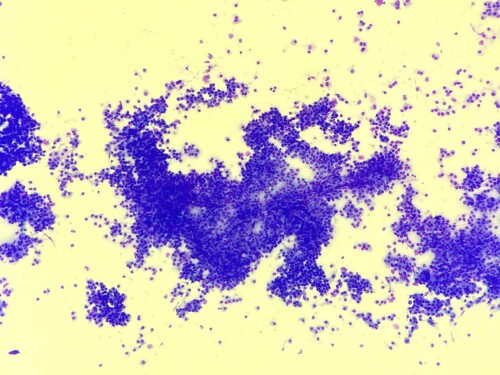

Un cas de plasmocytome canin

Elfie est une chienne Cocker Spaniel femelle non stérilisée de 12 ans présentée en consultation pour une masse cutanée sur le carpe non adhérente, de 1 cm